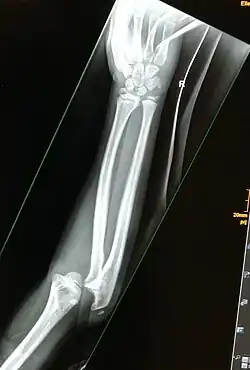

Beweisend sind Röntgenaufnahmen in zwei Ebenen, wobei seltene Formen (wie die hintere Schulterluxation) und kindliche Luxationen auch dabei schwer zu erkennen sind. Dann hilft eine Computertomografie (CT), Kernspintomographie (MRT) oder Arthrografie (besondere Röntgentechnik mit Einbringen eines Kontrastmittels in das Gelenk). Bei Kindern sind Luxationen im Ultraschall gut darstellbar.